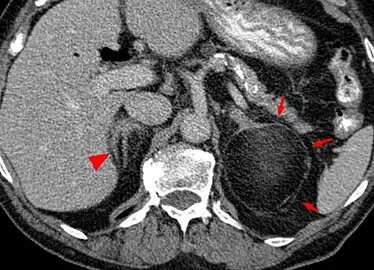

-

Myeloplipoma shown on a CT scan image -

Most myelolipomas are unexpected findings on CT scans and MRI scans of the abdomen. They may sometimes be seen on a plain X-ray films.[4]